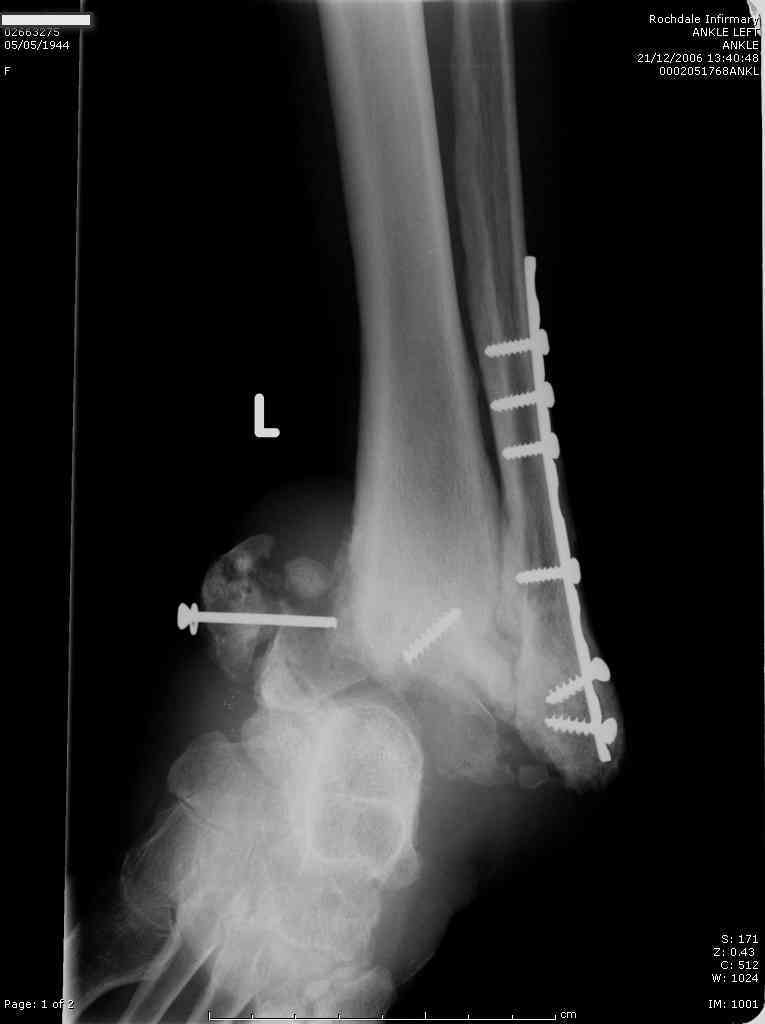

62 year old femaie, registered blind, IDDM with peripheral neuropathy, Diabetic nephropathy, and blindness - also most likely due to dabetic retinopathy, referred to me with deformity of the ankle and an ulcer on the lateral malleolus, No pain.

H/O ORIF both ankles 2 years ago for Bilateral ankle fractures. The otherside is doing well.

It is obviously a Charcot's ankle but what are the options? B K Amputation or a TTC fusion after removal of metalwork and healing of ulcer? Patient wants to walk and a bit reluctant for an amputation which is my preferred option. Any suggestions?